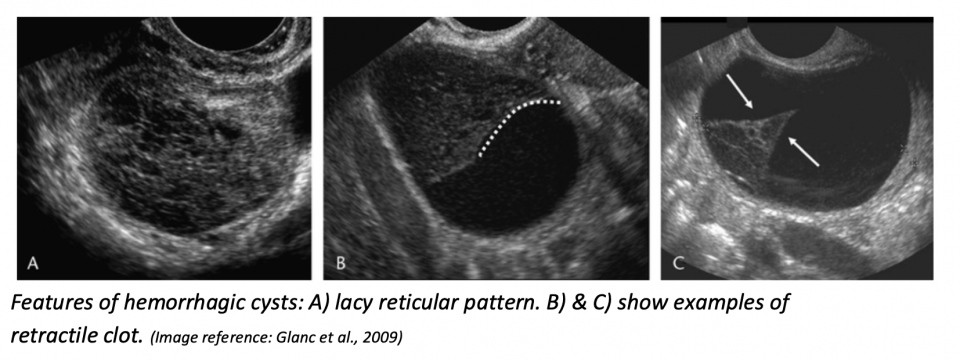

PoCUS features

Reticular or “lacy” pattern of fine internal echoes (“fishnet” or “cobweb” appearance) — due to fibrin strands from clotted blood

Fluid–fluid levels (from settling of blood products)

May show retracting clot: fibrin components contract, causing a concave, sharp, curvilinear or triangular internal mass that pulls away from the cyst wall

Usually no internal Doppler flow (but circumferential wall flow may be seen)